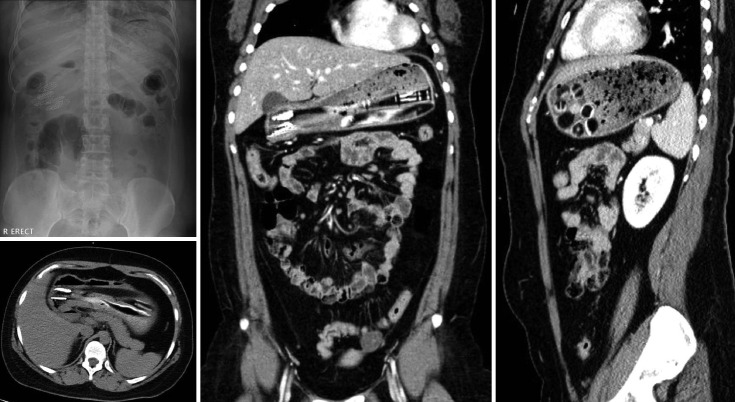

Foreign body ingestion is a common emergency that necessitates endoscopic intervention. Although many foreign bodies are easily removed, removal of magnets, blades, barbs, and unusually shaped objects, such as toothbrushes is challenging. Toothbrush ingestion may potentially cause complications such as pressure ulcers and perforations. We present a rare case of a 26-year-old woman with schizophrenia, who ingested multiple foreign bodies but was asymptomatic. Radiography showed multiple toothbrushes in the stomach. Emergency non-sedated endoscopy revealed eight toothbrushes in the stomach; five toothbrushes lodged in the great curvature of the stomach and three in the duodenal bulb were successfully removed using a snare and a technique that involved neck hyperextension to facilitate passage. This report describes a case of non-sedated endoscopic removal of multiple toothbrushes, which is rarely reported in the literature. This case highlights that even complex foreign bodies can be safely removed via endoscopy without surgical intervention. To our knowledge, this is the first report in the English literature that discusses endoscopic removal of more than five toothbrushes and underscores the role of customized approaches in the management of ingestion of unusual foreign bodies.